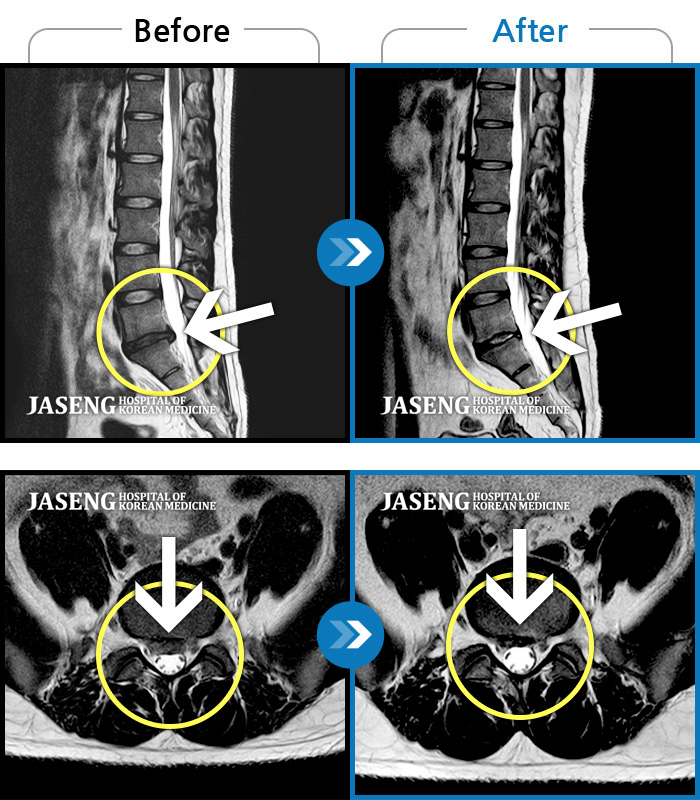

MRI ũ ʸ Ȯϼ.

ȯںп Ǹ ǿ ԿǾ, ο ġ ۿ Ƿ ġḦ Ͻñ ٶϴ.